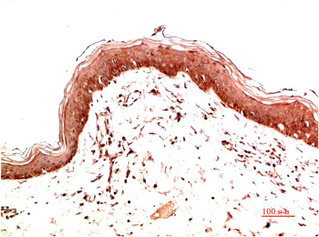

圖片:

產品描述:本產品為COL1A1單克隆抗體(CUSABIO貨號:CSB-MA952416),特異性識別I型膠原蛋白α1鏈(COL1A1),該蛋白是構成細胞外基質的主要成分,在維持組織機械強度、調控細胞黏附和信號傳導中發揮關鍵作用,尤其與纖維化疾病進程、腫瘤微環境重塑及骨代謝調控密切相關。該抗體經嚴格驗證,適用于ELISA和免疫組化(IHC)實驗,可精準檢測人、小鼠、大鼠等多物種樣本中COL1A1蛋白的表達定位及相對豐度,具備良好的批間穩定性和抗原結合特異性。科研領域可應用于纖維化疾病模型(如肝纖維化、肺纖維化)的機制研究、腫瘤基質成分分析以及骨組織工程中膠原代謝的動態監測,為探索細胞外基質相關信號通路及病理機制提供可靠工具。該COL1A1抗體采用高純度免疫原制備,確保低交叉反應性,適用于復雜組織樣本的多重標記實驗,滿足分子生物學、病理學及基礎醫學研究的多樣化需求。

應用范圍:ELISA,IHC

Application Recommended Dilution IHC 1:50-1:200 -